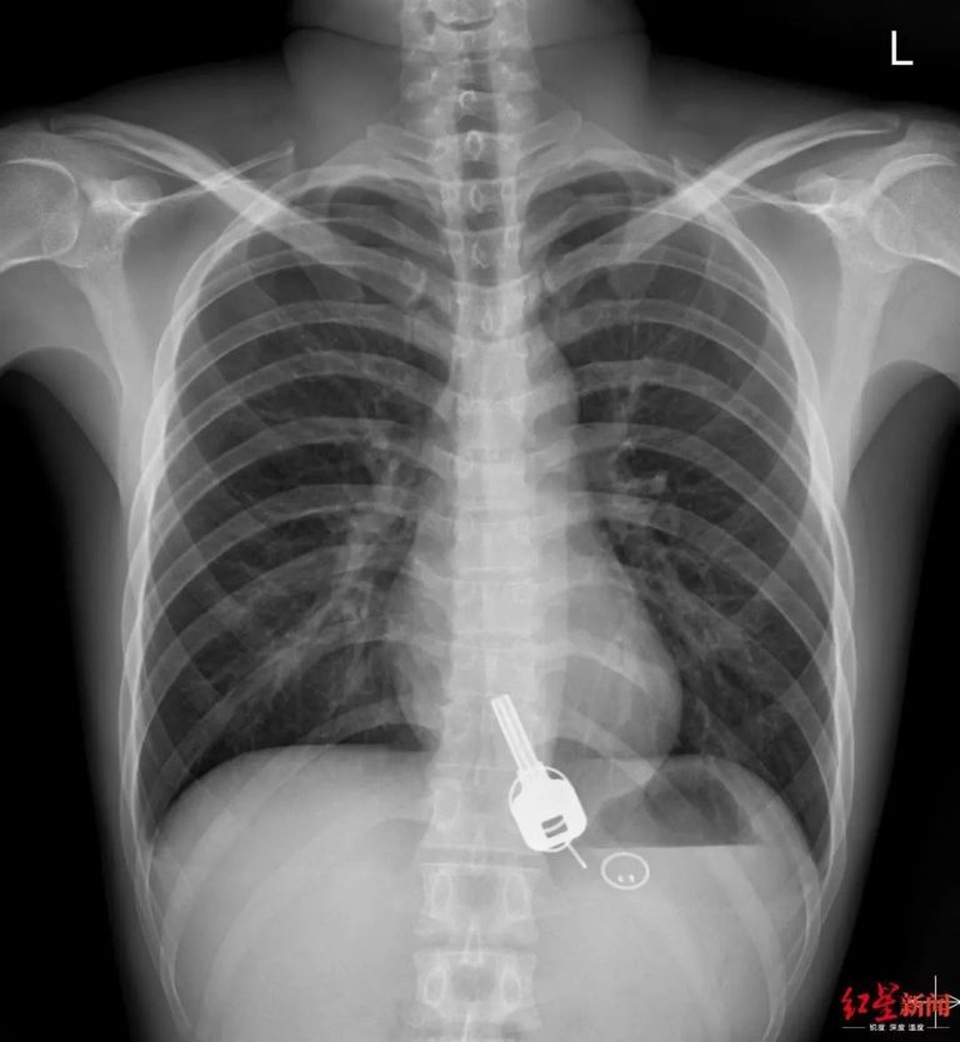

Khi các bác sĩ thực hiện chụp X-quang, họ đã thực sự bị sốc khi thấy một thứ trông giống như chìa khóa đang nằm trong thực quản của Chang. Họ hỏi về điều đó và thanh niên 26 tuổi thừa nhận đã đánh mất chìa khóa vào đêm hôm trước nhưng không thể đưa ra bất cứ lời giải thích nào về hành động nuốt chìa khóa của mình. Theo trang tin tức Sohu, Chang cũng bất ngờ không kém các bác sĩ khi nhìn thấy ảnh chụp X-quang.

Các bác sĩ tại bệnh viện Đông Hoản đã phân tích tình hình và quyết định để chìa khóa đi ra ngoài theo đường tiêu hóa và được loại bỏ theo cách tự nhiên là hết sức rủi ro, vì vật cứng như vậy có thể làm rách ruột hoặc gây tắc nghẽn ruột, đe dọa nguy hiểm tới tính mạng. Đồng thời, cố gắng kéo chìa khóa ra bằng thiết bị nội soi có thể làm vỡ thực quản của Chang. Lựa chọn thứ ba là phẫu thuật khẩn cấp.

Bác sĩ Zhang Yuyu nói với các phóng viên rằng lần đầu tiên, mọi người thử tháo chìa khóa bằng máy nội soi dạ dày nhưng họ gặp rắc rối khi cố gắng kéo chìa khóa qua phần hẹp nhất của thực quản trong cuống họng Chang. Chìa khóa quá lớn và kéo quá mạnh có thể làm rách thực quản, điều này sẽ gây ra hậu quả không thể tưởng tượng được.

Sau khi bác sĩ gây mê cho Chang sử dụng một loại thuốc giúp giãn cơ, bác sĩ tiêu hóa đã có thể rút chìa chìa khóa kim loại và tấm thẻ gắn kèm bằng nhựa ra khỏi thực quản chàng trai. Dù mọi chuyện đã kết thúc nhưng làm thế nào Chang có thể nuốt chìa khóa của mình vẫn còn là một điều bí ẩn vì anh hầu như không nhớ bất cứ điều gì sau đêm say rượu.